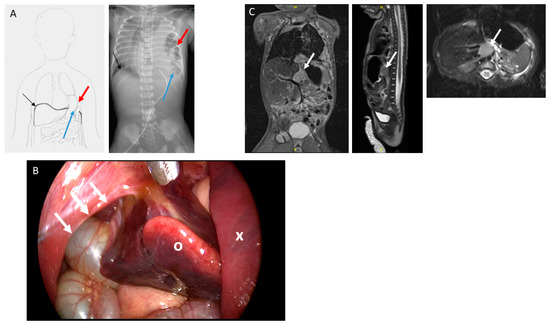

| Biopsy | Location | Tissue | Immunohistochemical | FISH | MGMT-STP27 | Hughes Classification | Evans Classification | Evaluation |

|---|---|---|---|---|---|---|---|---|

| 1 | Thoracically herniated mass | Liver metastasis | Synaptophysin + Tyrosinhydroxylase + NB84 + | NMYC not amplified | Unmethylated | Grade 3 | Poorly differentiated, stromal-poor neuroblastoma | |

| 2 | Retroperitoneal | Primary tumor | Synaptophysin + Chromogranin A + Neurofilament + | NMYC not amplified | Stage 4-S | poorly differentiated, stromal-poor neuroblastoma | ||

| 3 | Retroperitoneal | Primary tumor | Chromogranin A + | NMYC not amplified | Stage 4-S | Poorly differentiated, stromal-poor neuroblastoma |